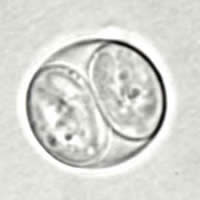

A: Toxoplasma gondii sporulated oocyst, unstained.

B: T. gondii sporulated oocyst, differential interference contrast (DIC), 100×.